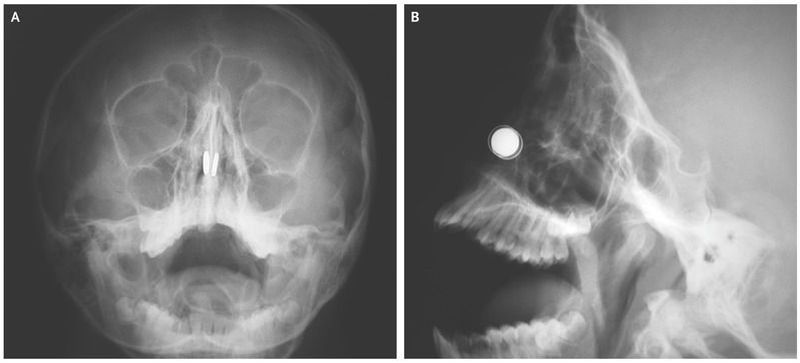

An 11-year-old boy was brought to the emergency department 6 hours after he had inserted button magnets in both sides of his nose. He had been unable to remove the magnets and presented with epistaxis and severe pain. Examination of the nasal cavity showed mucus and crusted blood. Radiography of the face revealed two disk-shaped foreign bodies at the same level across the nasal septum (Panel A shows the coronal view, and Panel B the sagittal view). Attracting nasal magnets necessitate emergency removal because they can compress the mucosa of the nasal septum, leading to necrosis and septal perforation. Attempts to remove the magnets in the emergency department were unsuccessful because of intense adherence, and the patient was taken to the operating room for removal of the magnets while he was under general anesthesia. The magnets were elevated off the nasal septum with the help of household magnets that were placed externally on both sides of the nose. The magnets had caused compression and mucoperichondrial erosion of the septal cartilage. Adhesion barriers were placed over the traumatized tissue surfaces, and splints were applied for 10 days. At follow-up 6 months later, the previously exposed cartilage was covered by healthy nasal mucosa.